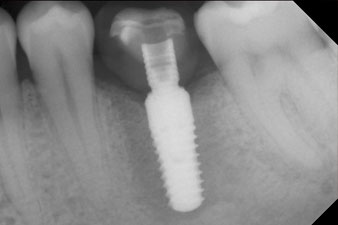

рентгенова проверка

Фиг. 10: Рентгеновата проверка показва успешна остеоинтеграция и короната е завита на място без празнина.